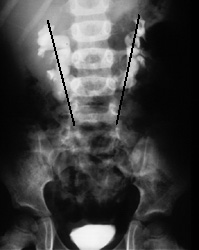

Horseshoe Kidney

| Horseshoe kidneys have an abnormal axis. Draw a line between the uppermost calyx and the lowermost calyx. In normal kidneys this line will be closer to the vertebral column at the upper pole. In horseshoe kidneys, the line will be closer to the vertebral column at the lower pole. | ![]()